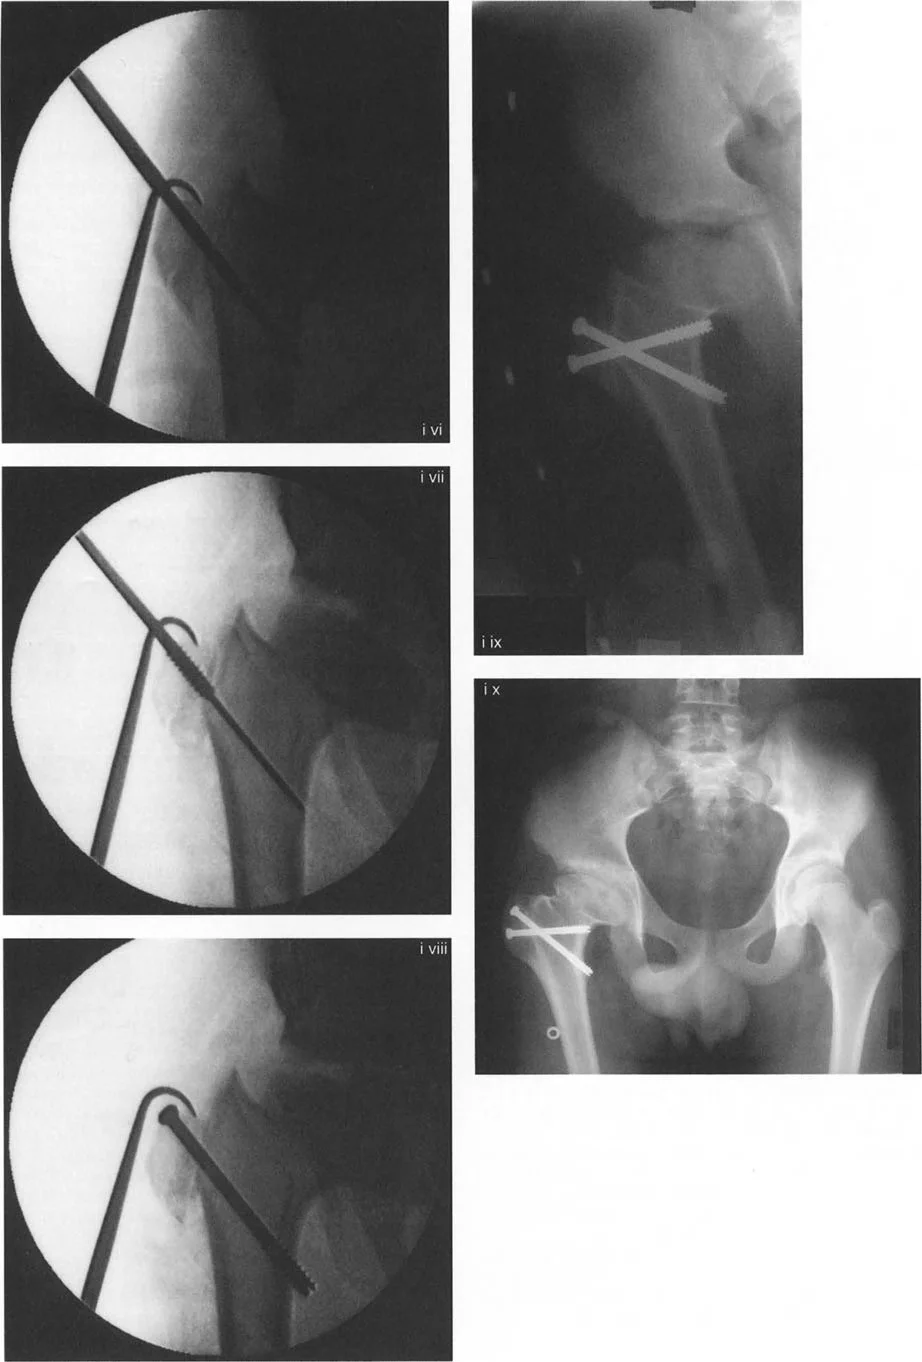

صور توضح حالة كسع الورك مع تضخم المدور الكبير قبل وبعد إجراء قطع عظم واغنر، حيث يتم تصحيح المحاذاة ونقل المدور الكبير.

صور توضح حالة كسع الورك مع تضخم المدور الكبير بسبب مرض بيرثيز، وعلاجها باستخدام قطع عظم مورشر مع التثبيت الداخلي.

تسلسل صور بالأشعة السينية يوثق تقنية نقل المدور الكبير بالمنظار، من إدخال سلك التوجيه والقطع إلى التثبيت بالمسامير.

صور بالأشعة السينية لحالة فتاة تعاني من تشوه فحجي مع دوران داخلي وخلع جزئي، توضح التدخل الجراحي بقطع عظم فاروسي مع نقل المدور الكبير والتثبيت بمثبت خارجي، ثم النتيجة النهائية بعد التعافي.

صور بالأشعة السينية لحالة كسع الورك مع رأس فخذ بيضاوي، توضح كيفية تصحيح اتجاه المحور البيضاوي بقطع عظم فحجي لتحسين توزيع الحمل.